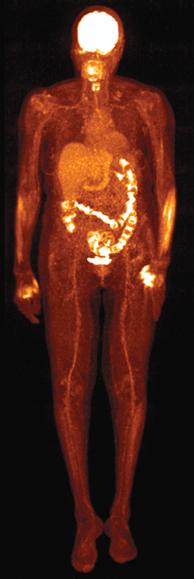

Siemens shone a spotlight on its Biograph mCT Flow PET/CT scanner for improvements in image quality and standard uptake values (SUV) thanks to a continuously moving patient table that ushers body areas steadily through the detector, producing a more reproducible and robust stream of data. The company’s Symbia Intevo single-photon emission computed tomography (SPECT)/CT leveraged the CT data set to create more accurate SPECT images, as well as combining the two data sets to allow, for the first time, accurate quantitation on a SPECT system.

What mCT Flow could do at the premium end of molecular imaging, Symbia Intevo might do for the masses performing bread-and-butter nuclear scans. Early adopters will see the benefit in bone scans, as Siemens has honed the technology first for this application. Other applications are expected to follow.